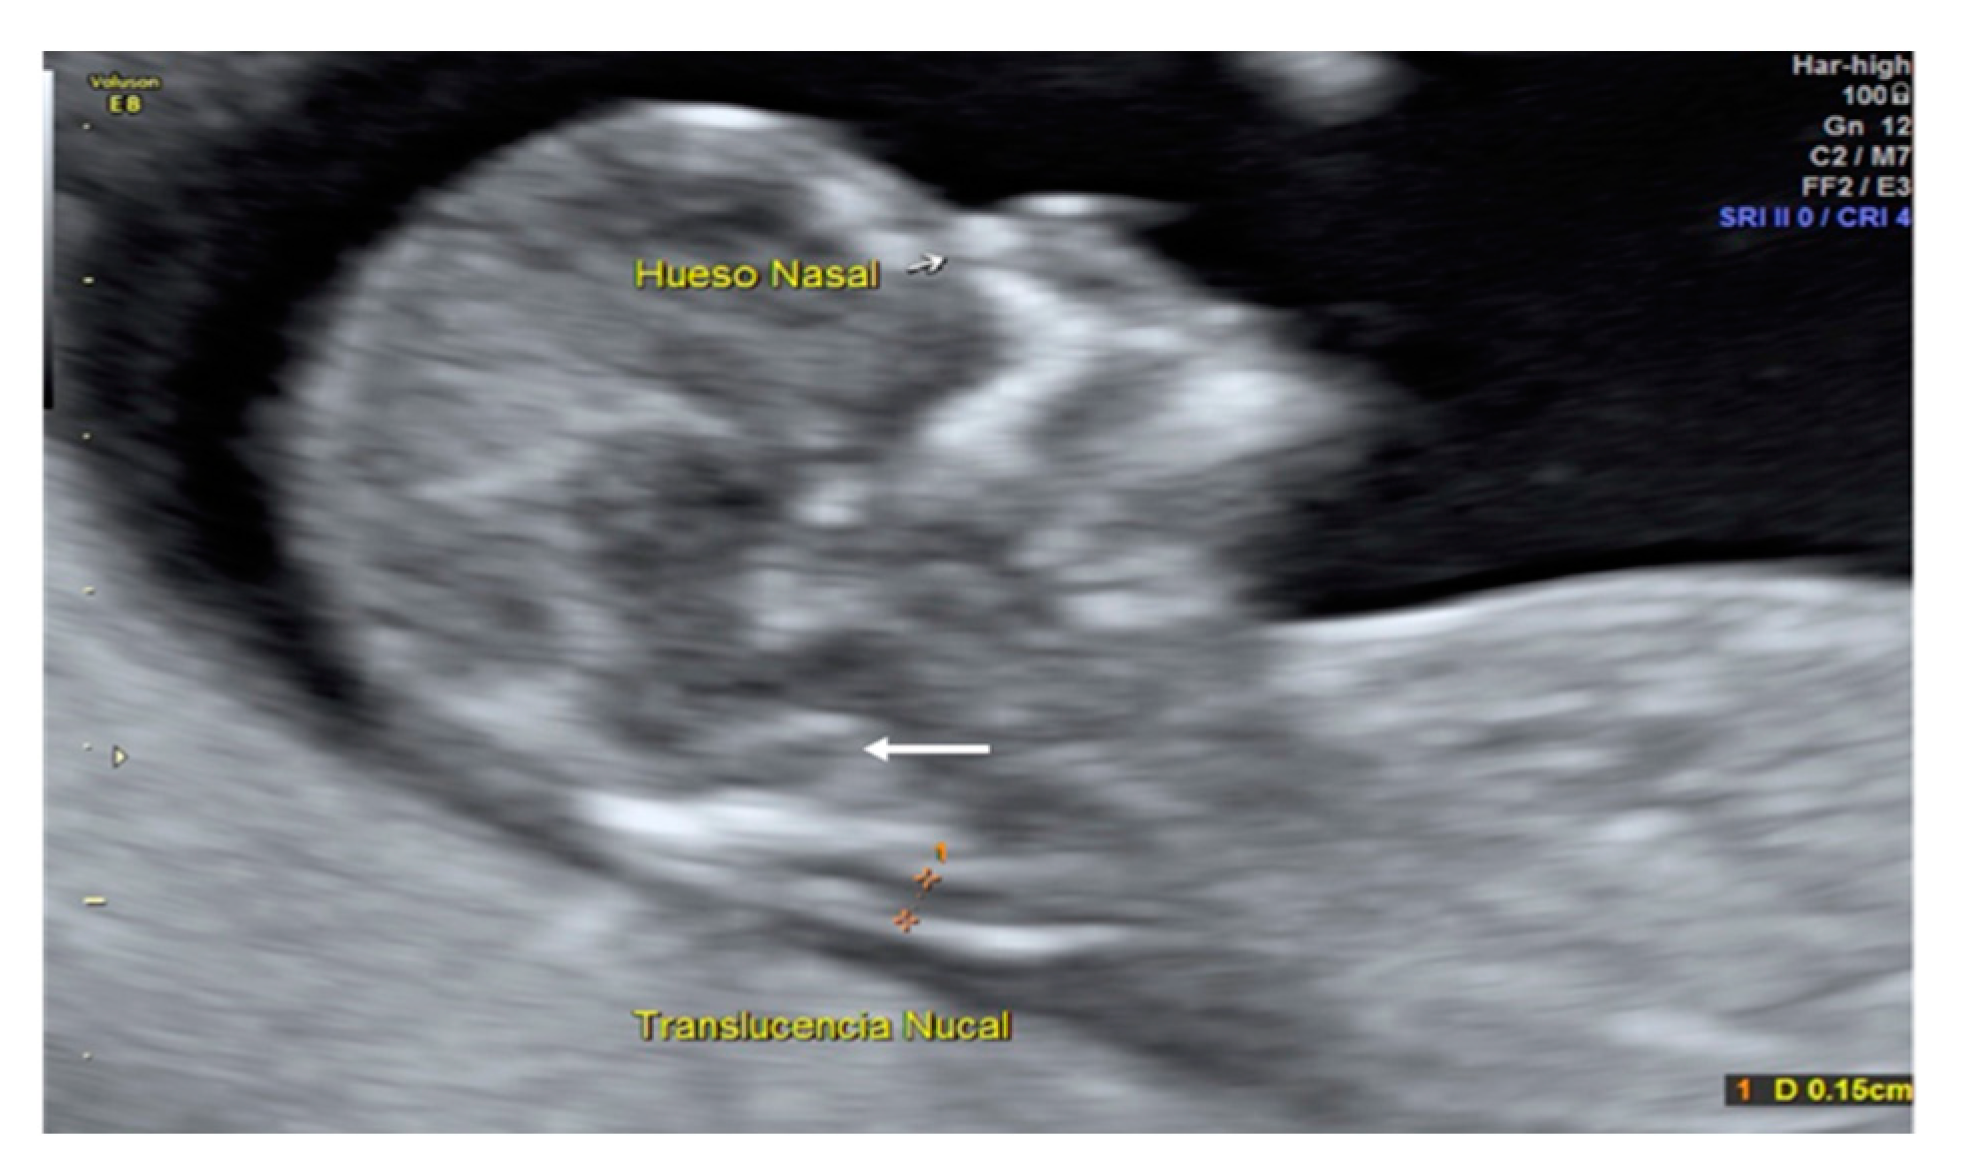

A 35-year-old patient, G3 P2 without relevant medical history was referred for first-trimester screening at 12 weeks of gestation. US findings were a crown–rump length (CRL) of 63 mm, NT of 1.5 mm, present nasal bone, and IT absence (Figure 2). The brainstem was thick, and the distance from the posterior border of the brainstem to the occipital bone was shorter than the brainstem diameter. No US markers for chromosomal anomalies were present. At 16 weeks′ gestation, the diagnosis of lumbosacral SBA was made. After medical counseling, the patient opted for pregnancy termination.

Figure 2. Case 1. First-trimester scan: Mid-sagittal view shows the thickness of the brainstem and a short distance from the posterior border of the brainstem to the occipital bone compared to the brainstem diameter (Big white arrow).